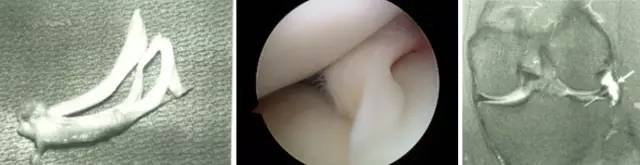

膝关节镜-半月板损伤

膝关节镜-前交叉韧带重建

膝关节镜-关节内游离体